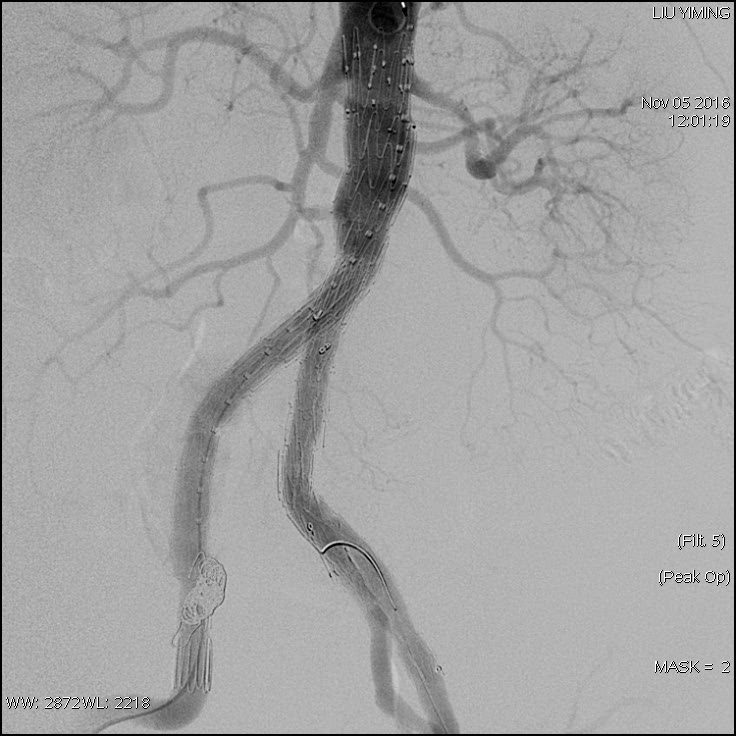

其中,在复杂主动脉病变腔内修复术应用手术直播中,郭伟教授带领其团队使用彩神在线网信彩票-彩神通免费版下载-彩神8争霸vlll-彩神购彩购彩大厅-彩神软件陆立根免费版-彩神ll争霸3-彩神ll彩神8-彩神ll争霸彩票-拼搏在线彩神网网页版科技公司的髂动脉分叉支架系统(IBD)以完全腔内重建的方式成功修复复杂腹主动脉瘤及髂动脉瘤。该例手术患者为64岁的男性,被诊断为肾下腹主动脉瘤,瘤体最大直径约6.5cm,双侧髂动脉瘤。患者成功植入彩神在线网信彩票-彩神通免费版下载-彩神8争霸vlll-彩神购彩购彩大厅-彩神软件陆立根免费版-彩神ll争霸3-彩神ll彩神8-彩神ll争霸彩票-拼搏在线彩神网网页版科技IBD支架,定位准确,无内漏,成功保留了左侧髂内动脉,术后造影显示髂内动脉通畅。

图:术前造影、术中造影、术后造影